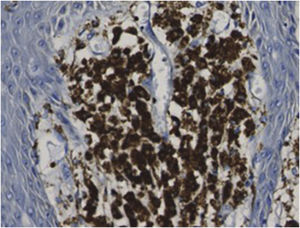

Um homem de 83 anos procurou cuidados médicos com queixa de múltiplos nódulos na bolsa escrotal, que apareceram pela primeira vez 20 anos antes. Eles estavam aumentando de tamanho e recentemente começaram a sangrar facilmente. O exame físico revelou dois nódulos vermelhos exofíticos e pedunculados, medindo 25×25mm e 13×13mm, que se projetavam de ambos os lados da bolsa escrotal (fig. 1). O paciente tinha história de câncer de próstata, cardiomiopatia hipertrófica obstrutiva, insuficiência aórtica, fibrilação atrial crônica, insuficiência renal crônica e tumores submucosos no esôfago. A histopatologia das lesões mostrou tumores exofíticos com acantose e papilomatose (fig. 2). As papilas dérmicas estavam ocupadas por numerosos histiócitos espumosos e hiperplasia de capilares (fig. 3). As células espumosas coraram‐se pelo ácido periódico de Schiff (PAS) e foram imunorreativas com o antígeno CD68 (fig. 4).

Considerando os achados histopatológicos, os nódulos foram diagnosticados como xantoma verruciforme (XV). Xantogranuloma foi excluído porque não foram observadas células gigantes do tipo Touton. Ambos os nódulos foram removidos cirurgicamente e mostraram as mesmas características histopatológicas. Nenhuma recorrência foi observada durante o seguimento de um ano.